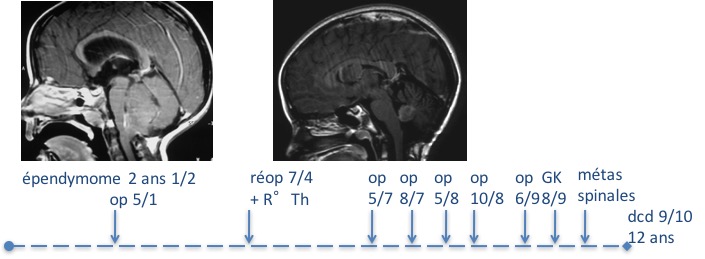

étant donné l’agressivité de ces tumeurs, la récidive doit faire poser systématiquement la question d’une réintervention.

techniquement, la réintervention est souvent facile si la tumeur est limitée au V4, elle est beaucoup plus risquée si elle adhère aux nerfs mixtes.

de même, une métastase unique n’est pas forcément une contre-indication à une réintervention, en particulier si elle fait courir un risque fonctionnel comme une métastase spinale.

le devenir après récidive dépend essentiellement de la possibilité ou non de réintervention ; si on peut réopérer l’enfant, le taux de survie sans récidive est globalement comparable à celui d’une première opération.

s’il s’agit d’un deuxième récidive, le pronostic est beaucoup plus sombre. une troisième intervention, voire plus, peuvent néanmoins se discuter, dans une logique compassionnelle, à condition de ne pas nuire à la qualité de la survie.